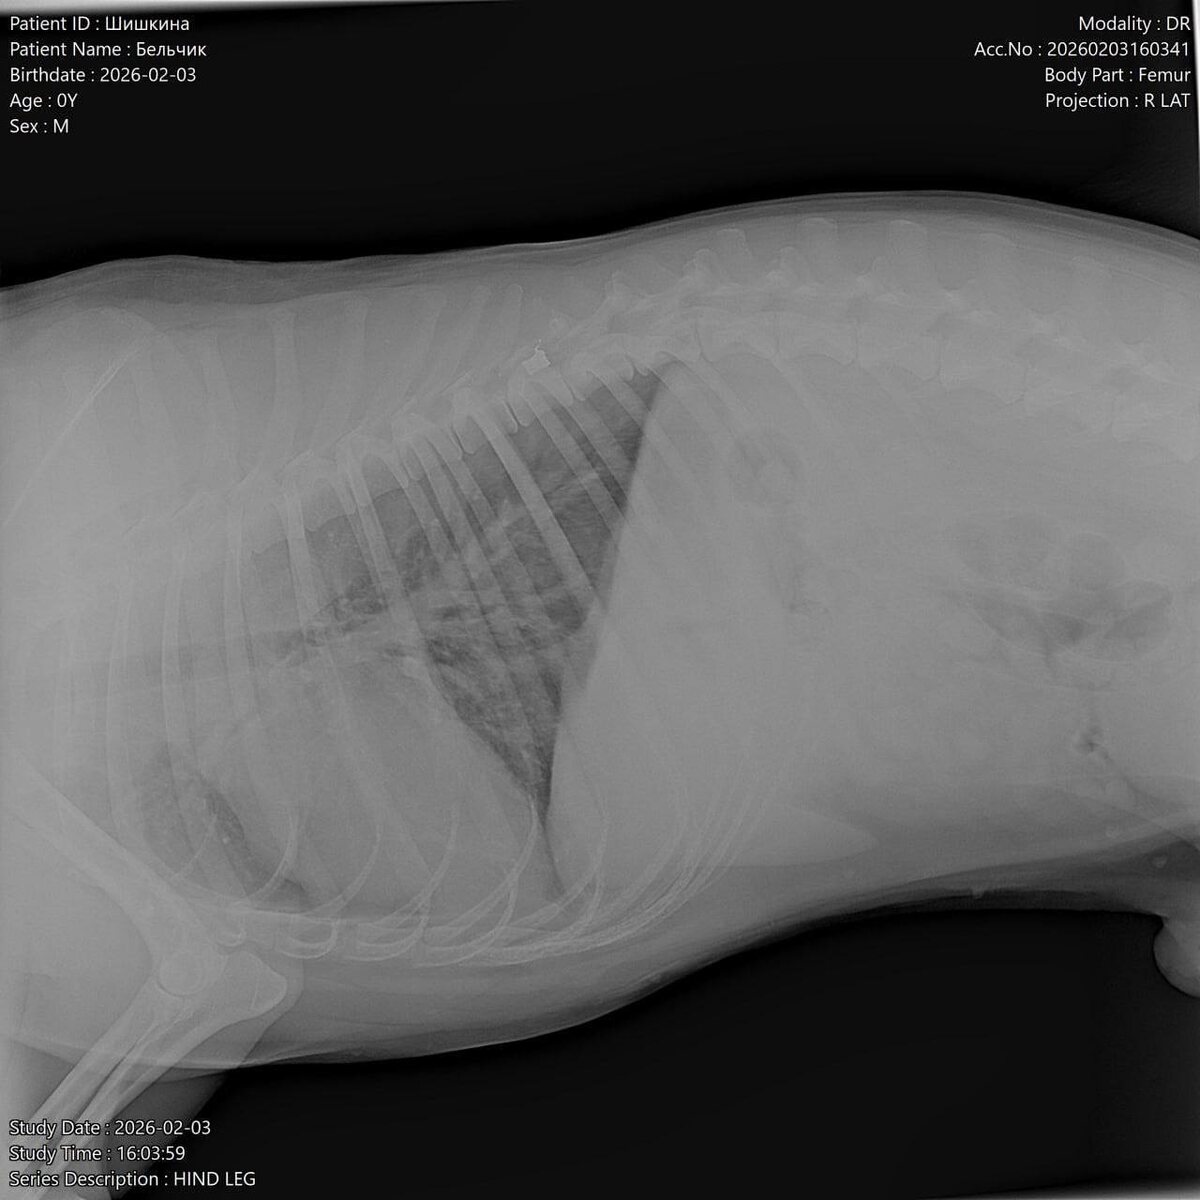

Сегодня, 4 февраля, в социальных сетях азовского приюта «Феникс» появилась информация о том, что днем ранее возле трассы рядом с кафе «Дорожное» была найдена собака, метис хаски или лайки, которая лежала и не двигалась. Изначально никаких повреждений визуально очевидцы не обнаружили, поэтому решили, что пса сбил автомобиль. Однако потом стало понятно, что животное не может встать на задние лапы и тянет их за собой.

Собаку привезли в ветклинику: рентген показал, что у пса пуля в позвоночнике и перелом таза.

«Что случилось, страшно представить, подстрелили, потом сбила машина... Бедное животное из последних сил выползло к людям в надежде на помощь. Просим правоохранительные органы отреагировать на ситуацию. Это не единственный случай на Мичуринце 3. Вместо того, чтобы вызвать отлов на собачью свадьбу, кто-то стреляет в собак, превращая их в пожизненных инвалидов. Собака может никогда не встать на лапы. Пёс добрый, адекватный. За что с ним так поступили и бросили в -15 на морозе», – написали волонтеры.